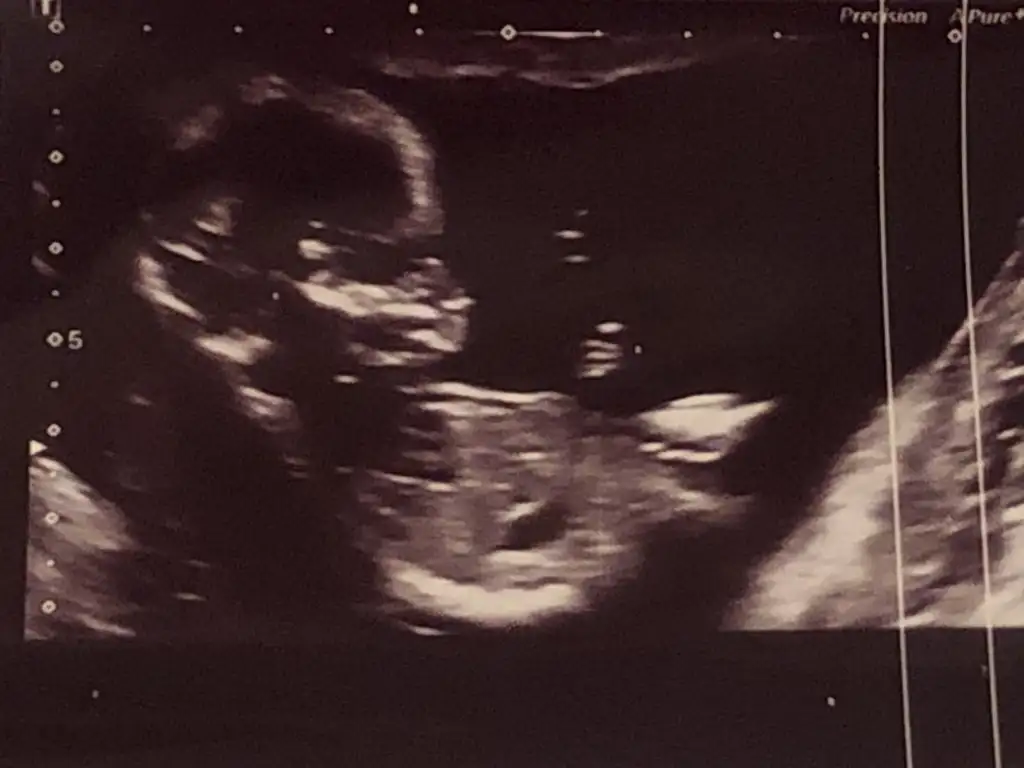

Banada cinsiyet tahmininde bulunabilir misininz Eki Görüntüle 2781088

Bana da bakar mısın lütfeeeen 13 ve 16 haftalıkSana yazacaktım msjı bulamadım benim yorumum bebek erkek nub teorisinde çıkıntı yukarda

Bana da yorum yapabilir miKız dedi.